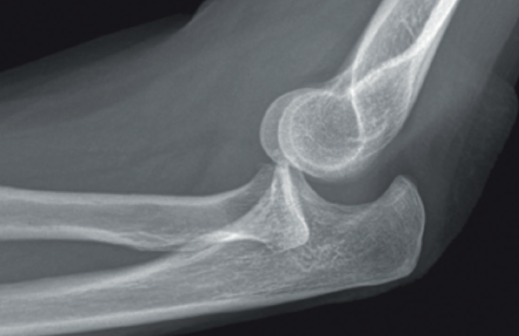

Y, por supuesto, signos directos, si objetivamos la articulación claramente subluxada (Figura 9).

Las radiografías de estrés forzando varo/valgo y buscando apertura dan muchos falsos positivos en casos de laxitud ligamentosa. - Resonancia magnética: es el gold standard para diagnosticar lesiones ligamentosas, con una sensibilidad del 57% y una especificidad del 100%.